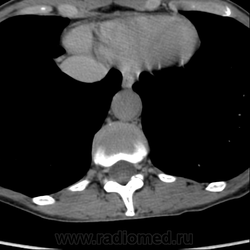

Выкладываю по очереди срезы на одинаковых уровнях, сначала паренхиматозная, потом отсроченная фазы.

Позвонил сейчас на работу, не выдержал. Коллега посмотрела - петля тонкой кишки 100%.